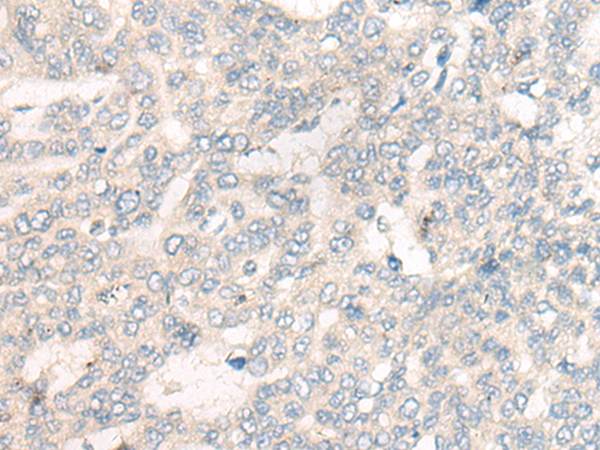

分类: 科研抗体货号: P13261别名: DSC; DSC1; DSC2; DSC4; CDHF3; HT-CP应用: IHC反应种属: Human, Mouse